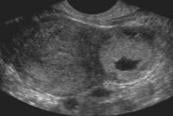

- Prior to the develop of a YS, a gestation sac (GS) becomes visible in weeks 4-5.

- Be careful not to rely on a GS as an IUP, 10-20% of ectopic pregnancies have pseudo-gestational sacs.8 (Video 8)

- Definitive evidence of an IUP is a gestational sac containing a yolk sac (YS) in two planes within the endometrium which usually occurs around 5-6 weeks gestational age.3,6 (Video 6 and 7)

- There is controversy with this definition; however, any earlier definition (eg, double decidual sign, empty gestational sac) is not accurate enough to ensure an IUP.7